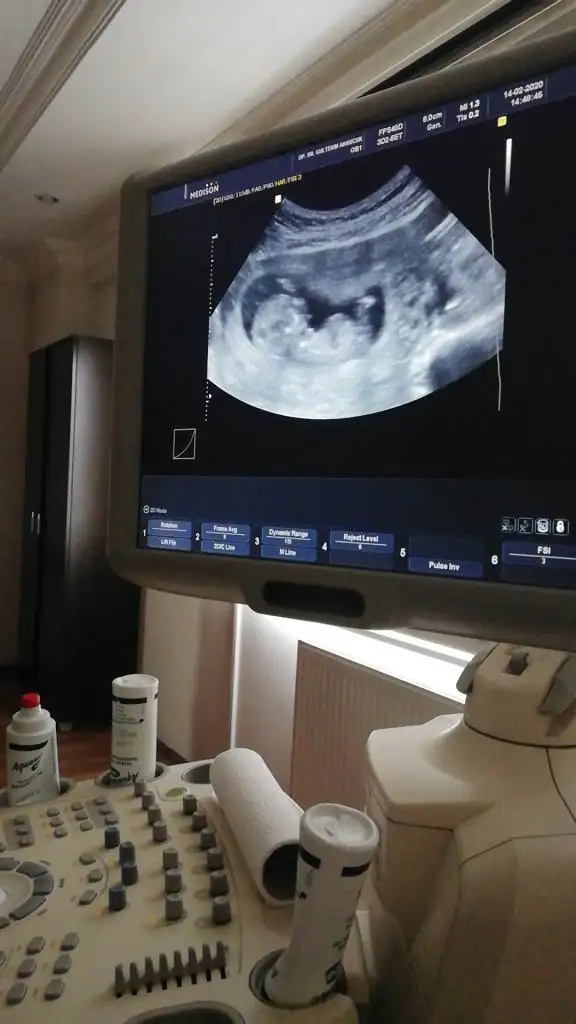

dr soylemeden siz gorun genital nub teorisi ( bebegin cinsiyeti)

Merhabalar Tahmin yorumlarınızı heyecanla takip ediyorum. Bende sabırla 12. haftamızın dolmasını bekledim. Bir yorumda benim için yaparmısınız Buğün 12+1 olduk.

Tam net değil usg dr çıktısı yokmu bu usglerde emin olamadım sanki diyerek kız gibi gibi tekrar usg bekliyorum

Var tabiki ama ne olmadığı için ekran fotoğrafı yolladım